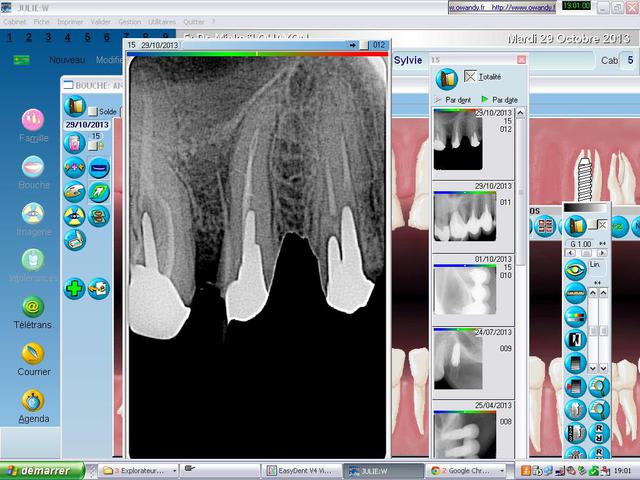

Ma patiente est venue en urgence avec une fistule purulente entre 15 et 16.

J'ai pris une radio avec cône de gutta dans la fistule. Le cône mène à une lésion osseuse latérale.

Je pense que cela provient d'un canal latéral ou d'une fracture.

Précise sur la radio entre 5 et 6 c un cône de gutta inséré dans la fistule

T'as pas une pêche au bout de 15? (située entre 15 et 14 au niveau des apex... au bout de la 14?)

Je dirais abcès endo avec voie de drainage latérale. RTE 15.

Edit. Je suis à peu près sûr que t'as un granulôme au bout de la 15.

Il y a déjà un canal latéral obturé. Si c'est lui la cause de la lésion, bon courage pour le désobturer......